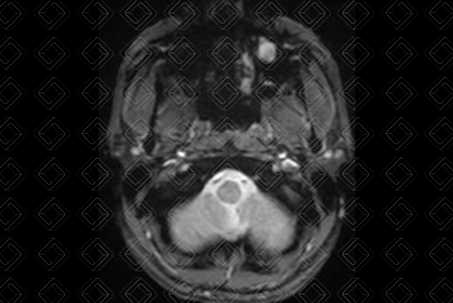

Texto alternativo para a imagem Figura 2. Créditos: Dra. Elazir Mota - Rio de Janeiro/RJ

Texto alternativo para a imagem Figura 3. Créditos: Dra. Elazir Mota - Rio de Janeiro/RJ

Descrição das figuras 2 e 3: Ressonância magnética da face, imagens ponderadas em T2, reconstruções axial e coronal, evidenciando imagem no assoalho do seio maxilar esquerdo, com sinal elevado em T2 (seta amarela).

• Ressonância magnética da face (figuras 2 e 3): Imagem também de contornos lobulados, com sinal variável nas imagens ponderadas em T1 (depende do conteúdo proteico) e alto sinal em T2 .